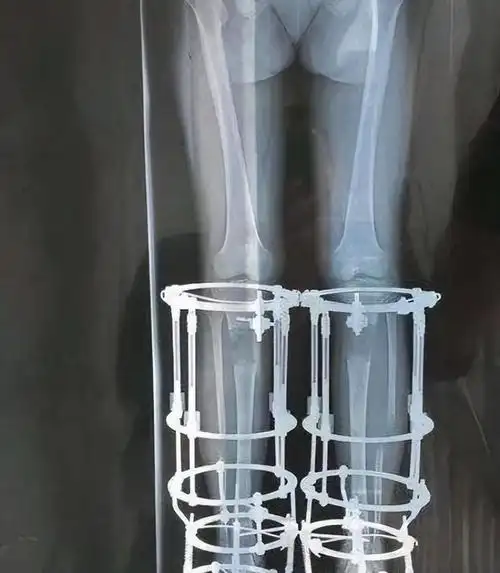

切断双腿骨头增高7厘米,结局如何|手术|医生|截肢|治疗_网易订阅